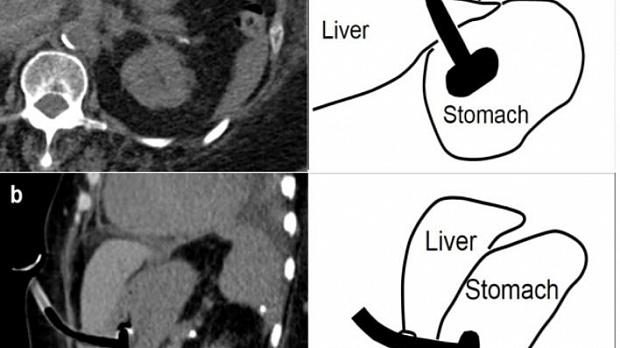

Чрескожная эндоскопическая гастростомия в настоящее время — стандарт в обеспечении пациента энтеральным питанием на длительное время. Осложнения при данном вмешательстве редки, одно из чрезвычайно редких — повреждение печени.

Авторами из США описано[1], как в результате установки 78-летней пациентке гастростомы трубка прошла через ткани печени. В анамнезе у больной — инсульт, сахарный диабет 2-го типа, гипертония и ожирение (индекс массы тела — 34 кг/м2), а показанием для гастростомии стали нарушения глотания.

В ходе процедуры пациентка лежала на спине. Проведенная после вмешательства КТ брюшной полости показала, что гастростомическая трубка пересекла боковой край печеночного сегмента 3 с прилегающей гематомой размером 2 × 2 × 4 см (рис. 1).

Рисунок 1 [1].

При обследовании брюшной полости трубка PEG свободно вращалась, зона вмешательства была чистой и сухой — без крови и наличия содержимого. Уровень гемоглобина оставался стабильным. Энтеральное питание начали вводить через 24 часа после процедуры без осложнений. Пациентка была выписана.